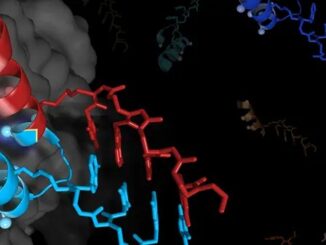

Nova tecnologia pode revolucionar vacinas personalizadas e terapias contra o câncer, melhorando a resposta do sistema imunológico. Por Paloma de Sá |GNEWSUSA Pesquisadores da Universidade […]